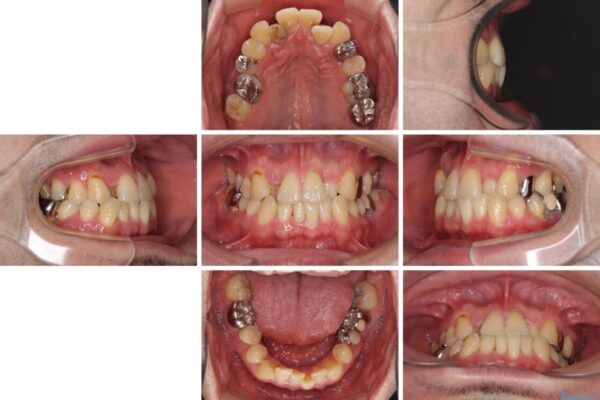

奥歯の痛みと前歯のデコボコを気にして来院された患者様です。

左右下顎の大臼歯は、ともに歯根が破折しており、抜歯が必要な状態でした。

放置したことで炎症による骨吸収が顕著であるため、骨造成を併用してインプラント埋入を行うこととしました。

咬み合わせは受け口傾向であり、上顎前歯の叢生が顕著であったことから、第1小臼歯抜歯による矯正治療も検討しましたが、下顎大臼歯を左右ともに抜歯するため、非抜歯による矯正治療を行うこととしました。

治療前

• 割れてしまった奥歯とデコボコの前歯 矯正治療とインプラント治療 治療前画像